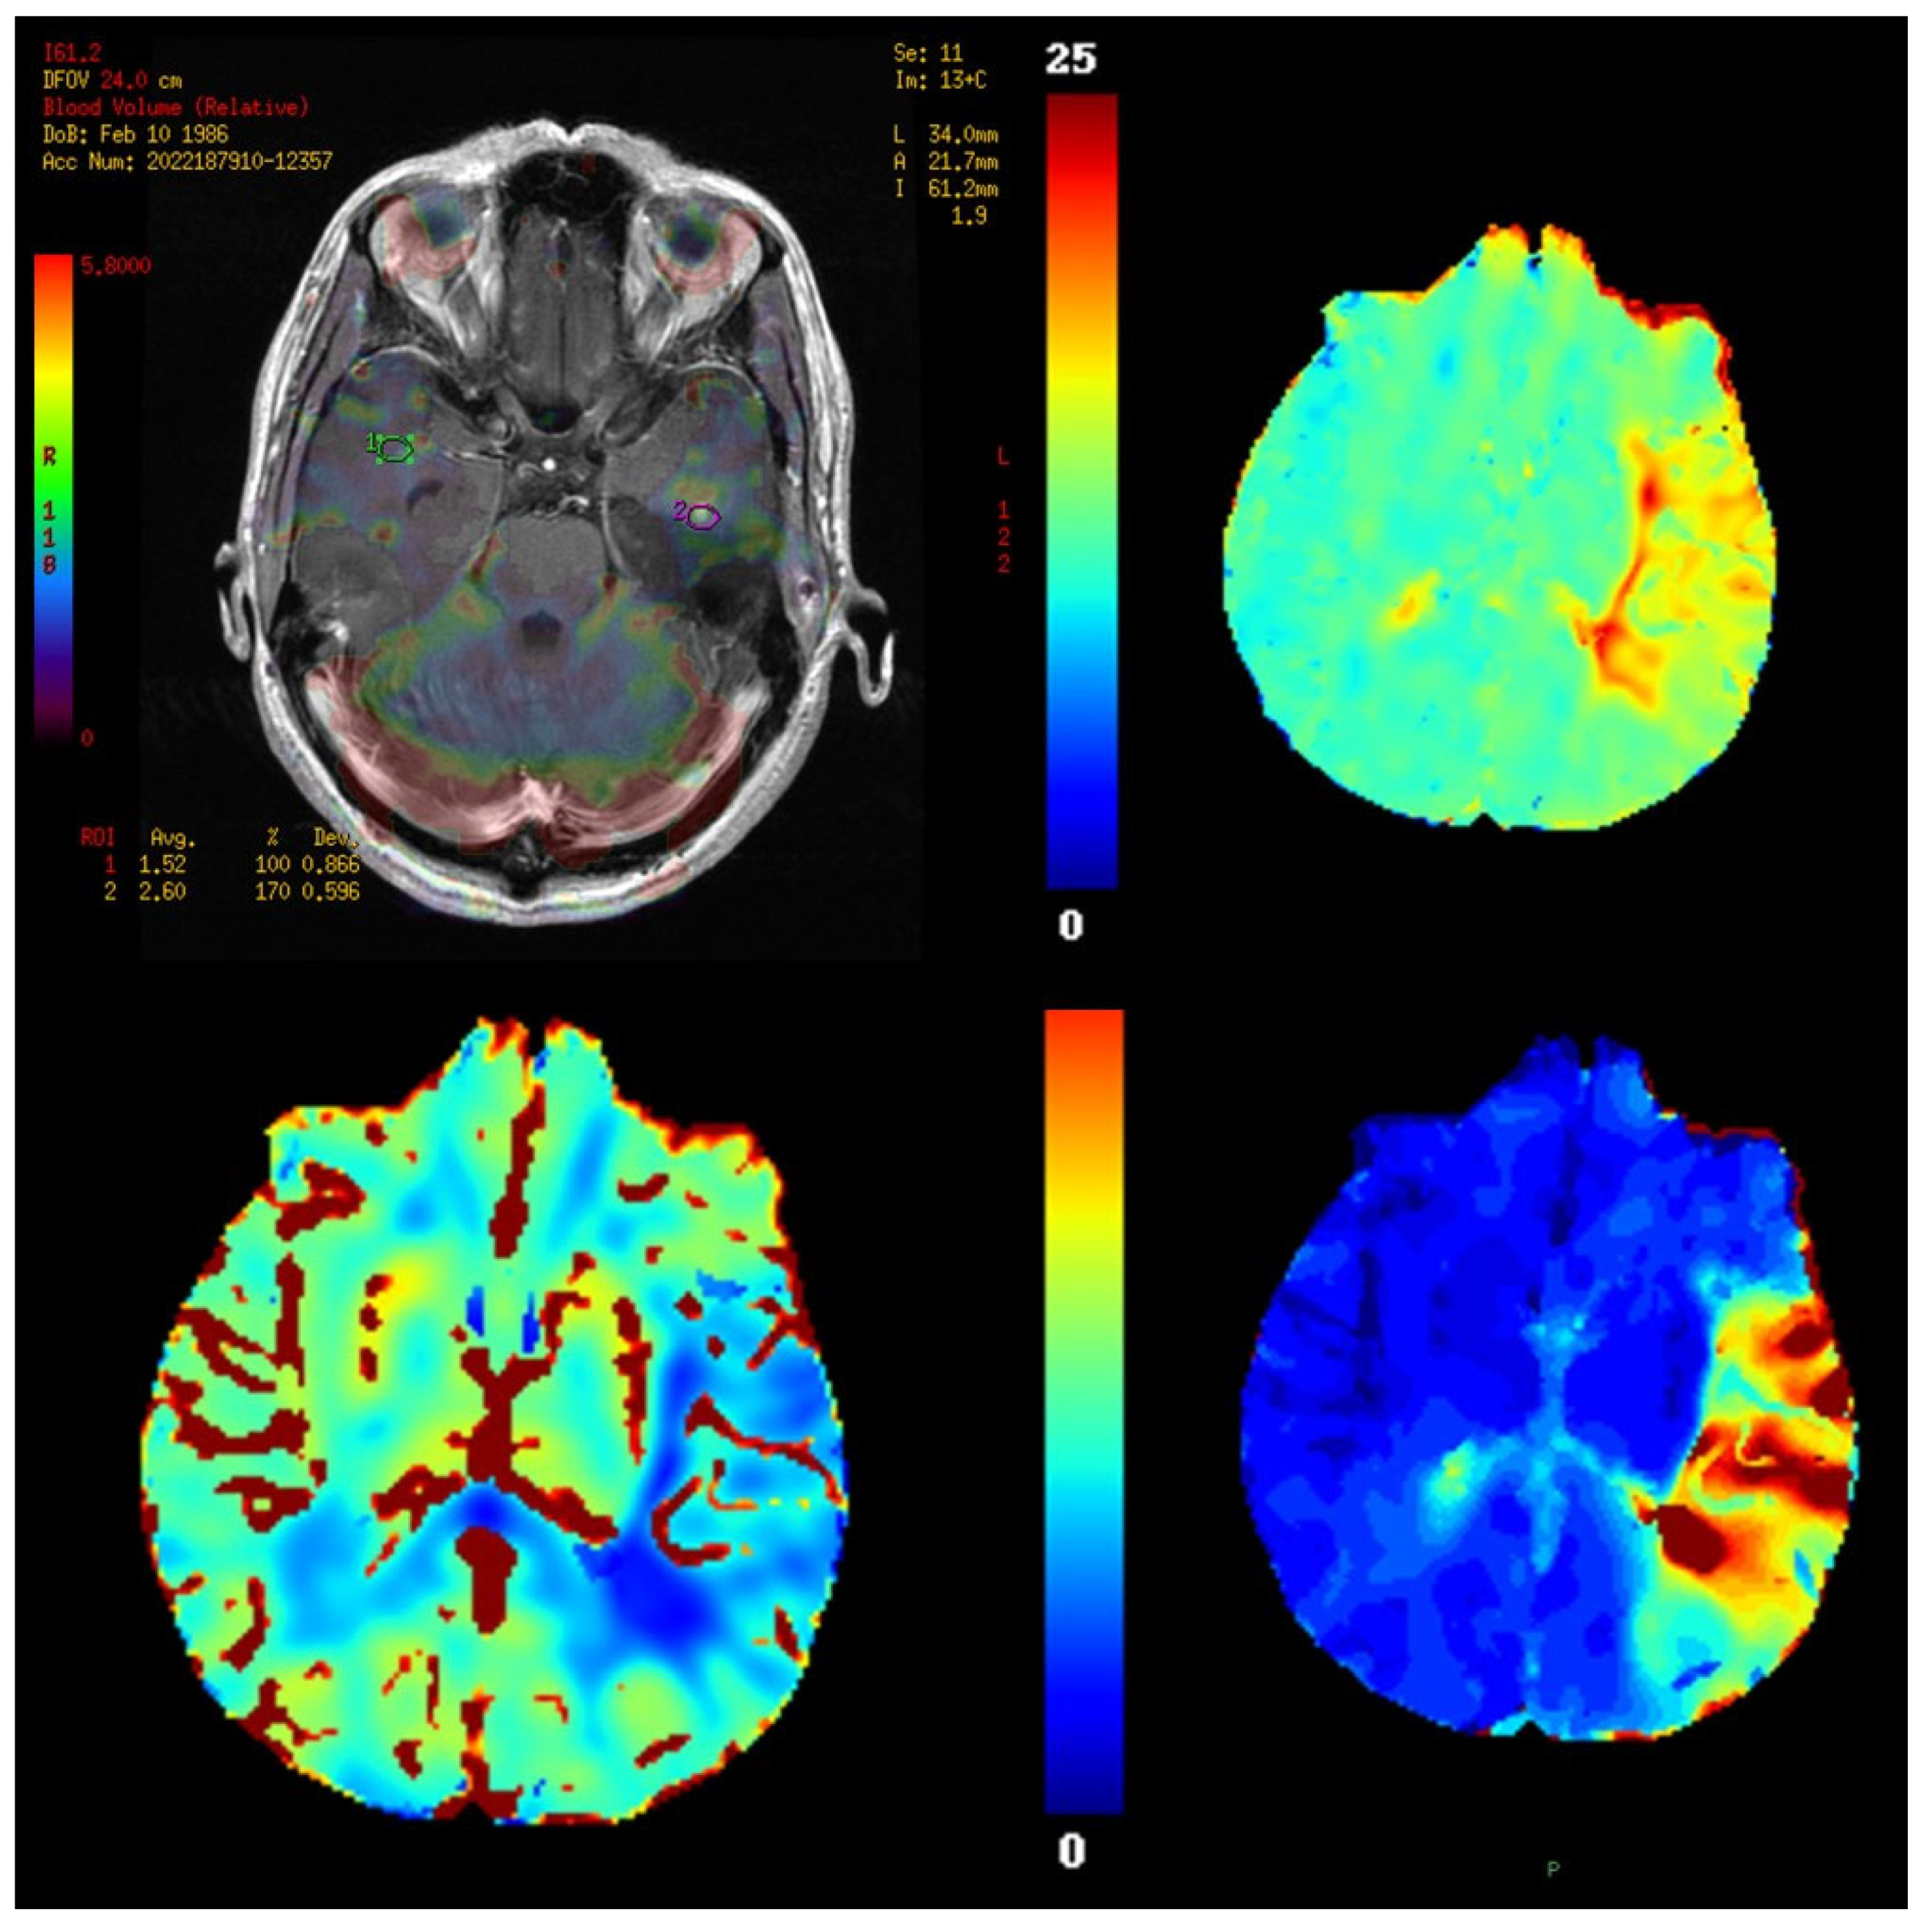

11. Perfusion Imaging

11.3. Outputs and Units

11.4. Validation and Quantification Considerations

11.5. Clinical Applications

- Lupo, J.M.; Cha, S.; Chang, S.M.; Nelson, S.J. Dynamic Susceptibility-Weighted Perfusion Imaging of High-Grade Gliomas: Characterization of Spatial Heterogeneity. Am. J. Neuroradiol. 2005, 26, 1446–1454. [Google Scholar]

- Stokes, A.M.; Bergamino, M.; Alhilali, L.; Hu, L.S.; Karis, J.P.; Baxter, L.C.; Bell, L.C.; Quarles, C.C. Evaluation of single bolus, dual-echo dynamic susceptibility contrast MRI protocols in brain tumor patients. J. Cereb. Blood Flow Metab. 2021, 41, 3378–3390. [Google Scholar] [CrossRef]